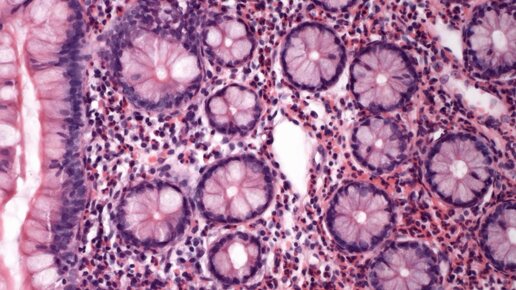

Эозинофильный гастрит

Определение Эозинофильный гастрит является редким воспалительным заболеванием, характеризующимся желудочно-кишечными расстройствами и эозинофильной инфильтрацией желудочно-кишечного тракта. Заболеваемость и смертность 1. Редко пациенты могут испытывать острую абдоминальную боль и перфорацию. 2. Желудочно-кишечные кровотечения. Пол, раса, и возраст 1. Пациентам обычно от 20 до 50 лет. 2. Педиатрическая пораженность в среднем 15-20% случаев. 3. Отношение «мужчина-женщина» 1: 1. Клинические проявления 1...